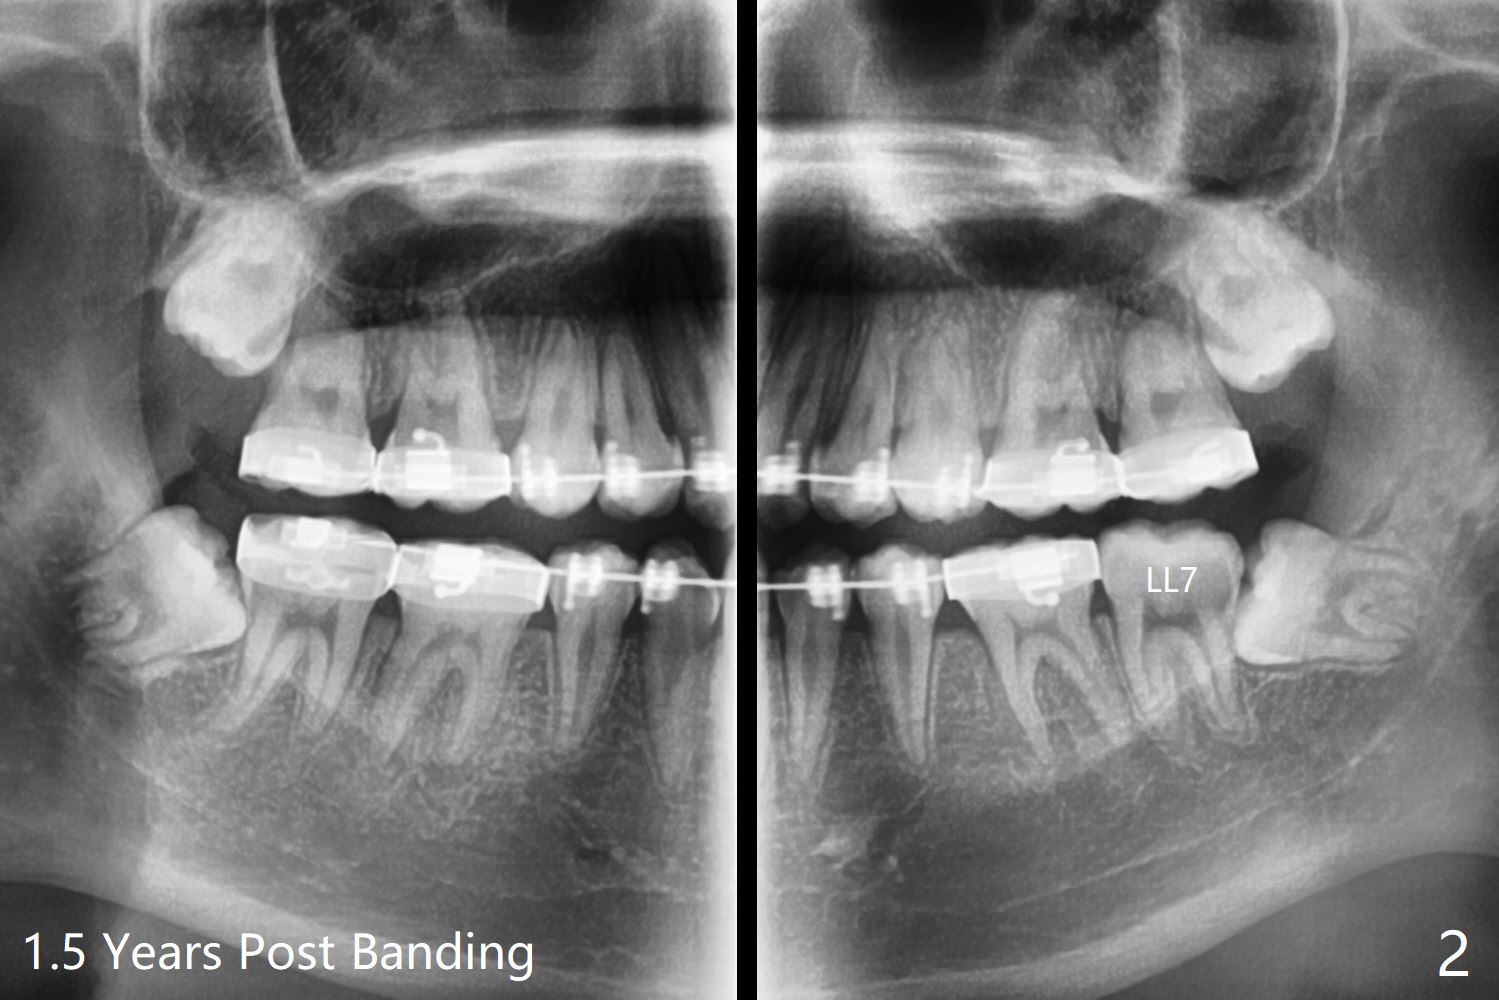

It is difficult to place a molar band in the lower left 2nd molar of a 15-year-old man after separators (Fig.1,2). It is due to the impacted 3rd molar.